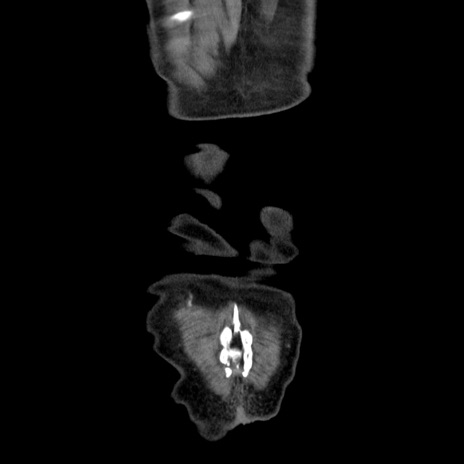

症例30(冠状断像)

横断像